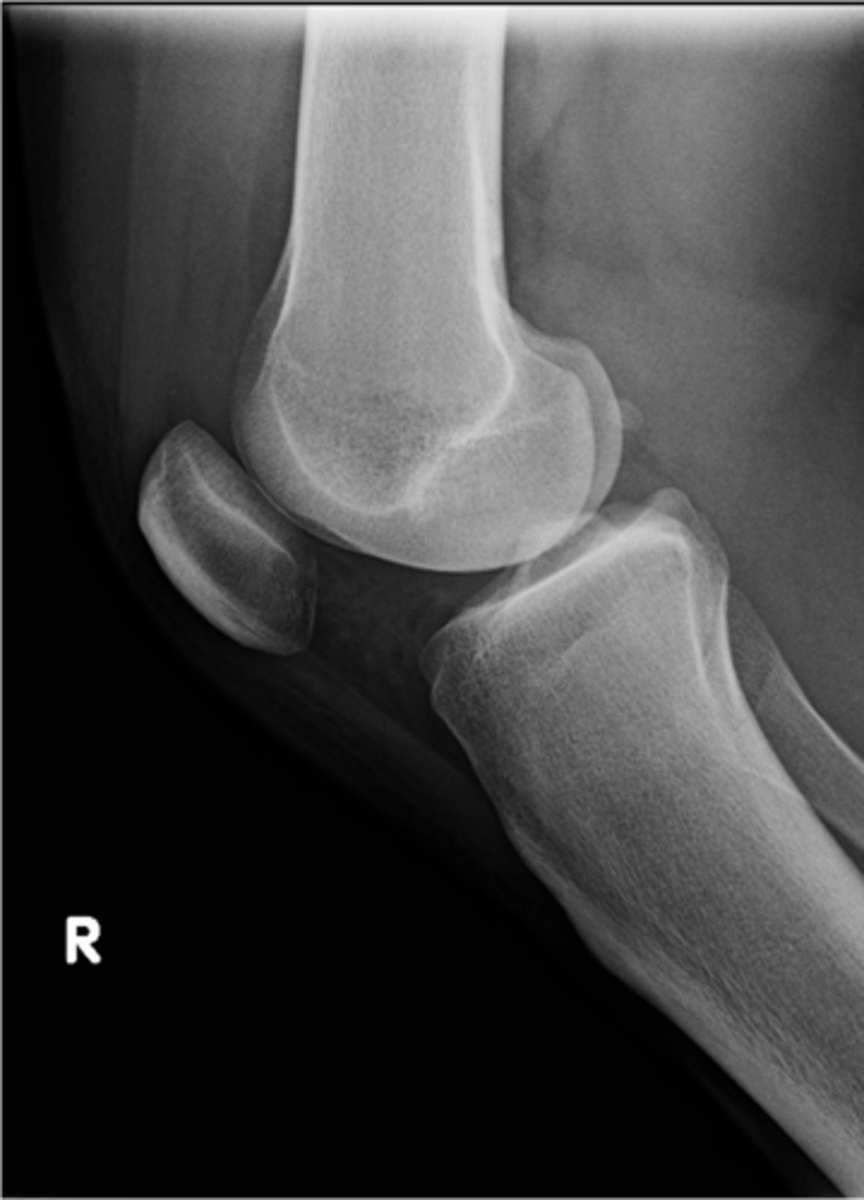

Right lateral knee

View?

68

New cards

Tibial tuberosity

ID 19

69

Intercondylar eminence

ID 20

70

Both tibial condyles

ID 21

71

Fibular head

ID 22

72

Apex of patella

ID 24

73

Superior aspect of patella

ID 25

74

Ludloff's spot/patch

ID 27

75

Apex of fibular head

ID 28